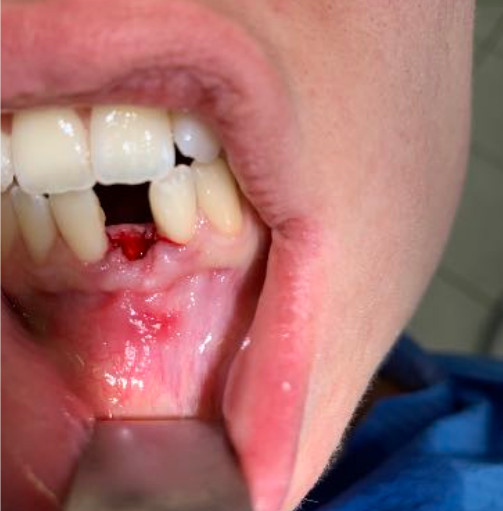

Il diametro ridotto del collo consente di mettersi al riparo da eventuali periimplantiti e migliora nettamente la velocità della guarigione. In questo caso è stato maschiato con un diametro 4 ed è stato inserito un impianto di Tramonte diametro 4 mm a 7 spire a collo corto . Il titanio utilizzato è sempre di grado 4.

| Saldatura : No | Zona dentale: incisivo inferiore 31 |

| Situazione estrattiva: Impianto postestrattivo immediato a carico immediato. | Densità secondo Misch: D2 |

| Sequenza frese: Solo fresa lanceolata | Sequenza maschiatori: maschiatore diametro 4 mm |